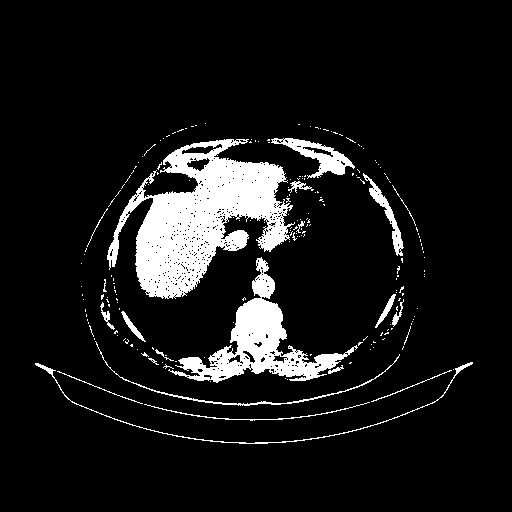

Original VENOUS CT scan

Full window (WL 1023.5, WW 4095 β†’ Low βˆ’1024, High +3071)

Actual HU range: [-1024.0, 3071.0]